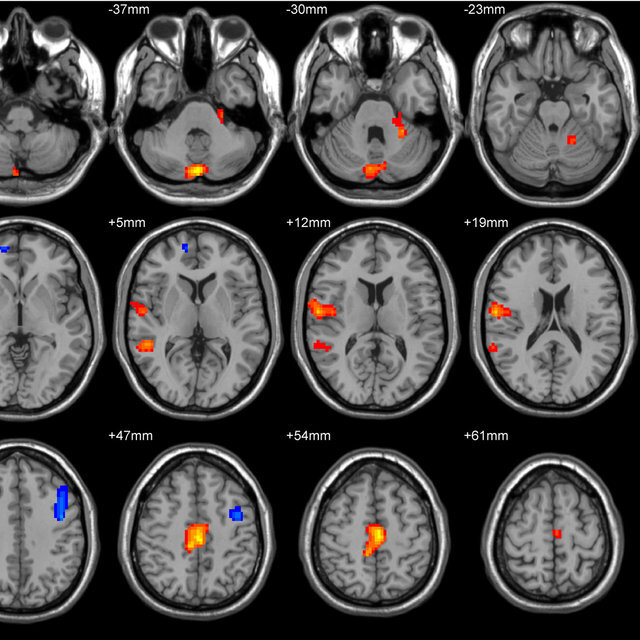

В ходе экспериментов на животных они обнаружили, что в результате химиотерапии врождённые иммунные клетки мозга – микроглии – заменяются другими иммунными клетками. Все полученные данные были опубликованы в издании Nature Medicine.

Результаты данного эксперимента показали, что после химиотерапии с применением бусульфана микроглиальные клетки утрачивают способность к регенерации. Более того, многие подобные клетки стареют и умирают.

Однако после трансплантации все исчезнувшие клетки быстро замещаются другими иммунными клетками, то есть клетками костного мозга – макрофагами. После этого макрофаги начинают выполнять функции, которые были характерны для микроглиальных клеток. Поэтому для мозга химиотерапия при трансплантации безвредна.